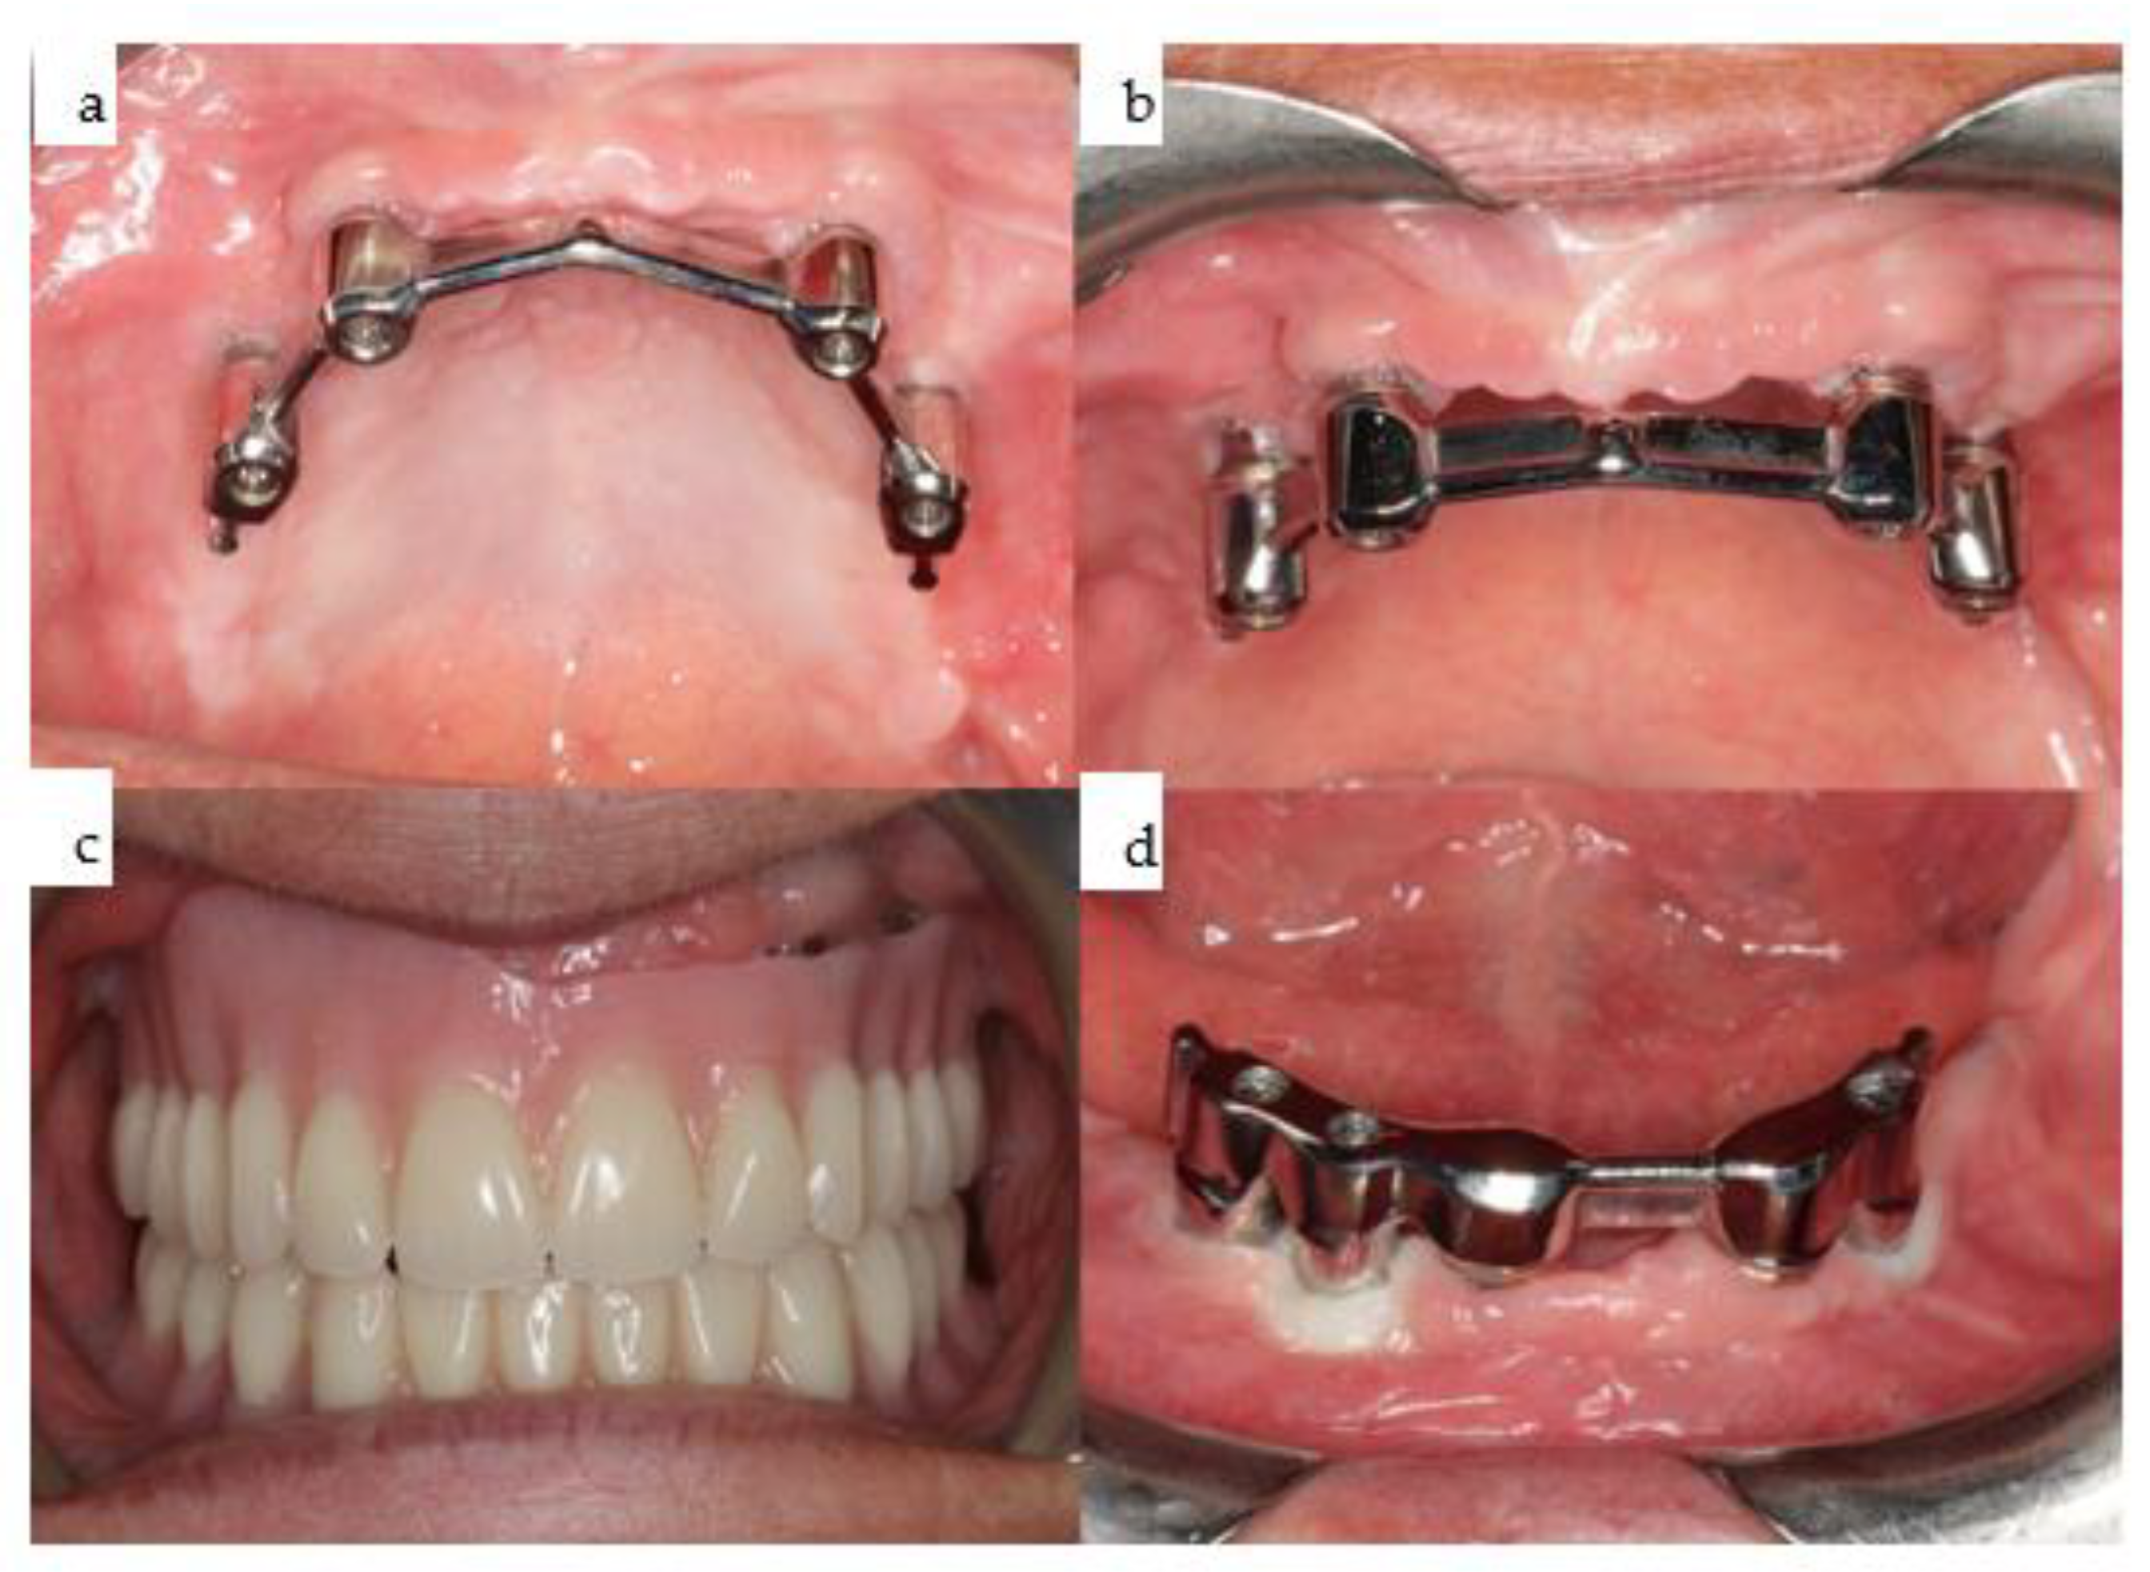

Figure 9. (ad): Four intraoral views showcase the healthy tissues surrounding the four posts of the one-piece subperiosteal IPS Implants® Preprosthetic (KLS Martin-Group, Tuttlingen, Germany). A bar-retained overdenture is utilized for both the maxilla and mandible (ac), with the hard palate left uncovered. The maxillary bar is screw-retained on the four posts (a,b), while in the mandible, the bar is screw-retained on the three secondarily inserted implant abutments and telescoped onto the two previously placed implants placed elsewhere (d).